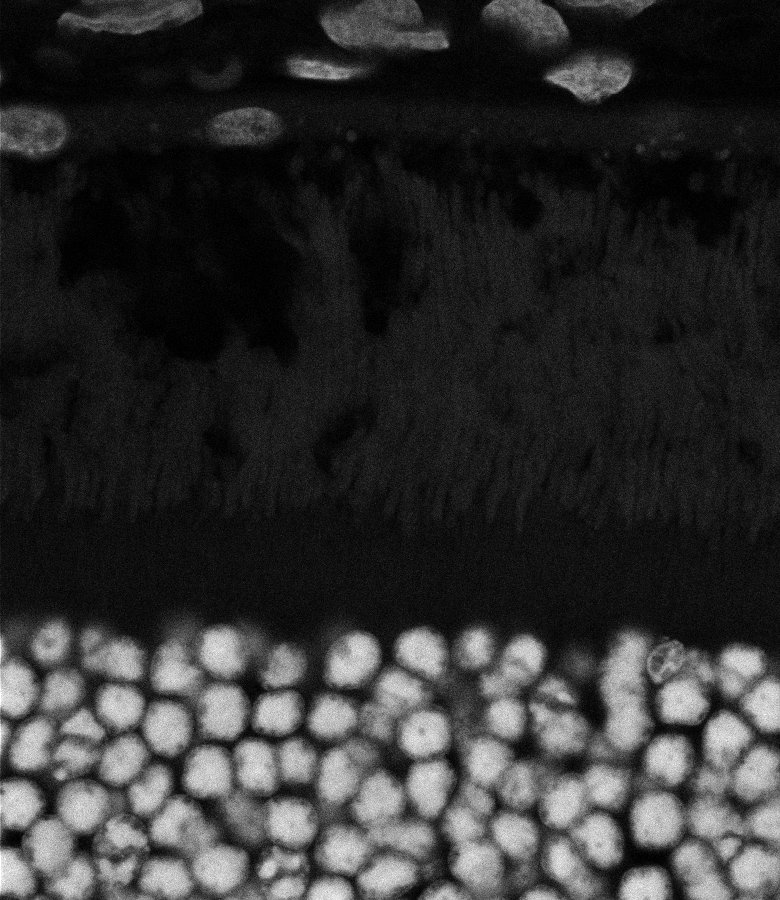

Healthy Retina

Unhealthy Retina

Healthy Eye

Blast Eye